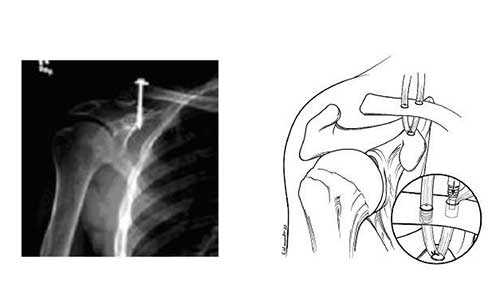

Ωστόσο μερικοί χειρουργοί προτείνουν την άμεση χειρουργική σταθεροποίηση χρησιμοποιώντας βίδα ή ράμματα.

Στις κακώσεις 4ου και 5ου βαθμού με σοβαρή διάσταση της ακρωμιοκλειδικής, υπάρχει μεγαλύτερη πιθανότητα πόνου και περιορισμένης λειτουργικότητας μόνο με την συντηρητική αγωγή, και η χειρουργική επέμβαση είναι η πιο λογική λύση.

Όταν η διάσταση της ακρωμιοκλειδικής είναι χρόνια (περισσότερο από μερικούς μήνες), η άρθρωση ανακατασκευάζεται και αποκαθίσταται χρησιμοποιώντας:

- Είτε τοπικούς συνδέσμους (αυτομοσχεύματα)

- Ή πτωματικούς τένοντες (αλλομοσχεύματα) σε συνδυασμό με ισχυρά ράμματα

Αρκετοί χειρουργοί πλέον ακολουθούν την δεύτερη επιλογή που αναφέρθηκε (αλλομοσχεύματα) δεδομένου ότι δημιουργεί μια ισχυρότερη τοπική ανακατασκευή των συνδέσμων της άρθρωσης. Οποιοδήποτε μόσχευμα και αν χρησιμοποιηθεί, η επέμβαση μπορεί να πραγματοποιηθεί είτε με συνδυασμό αρθροσκοπικής και ανοιχτής μεθόδου ή με μια εντελώς ανοιχτή χειρουργική επέμβαση.